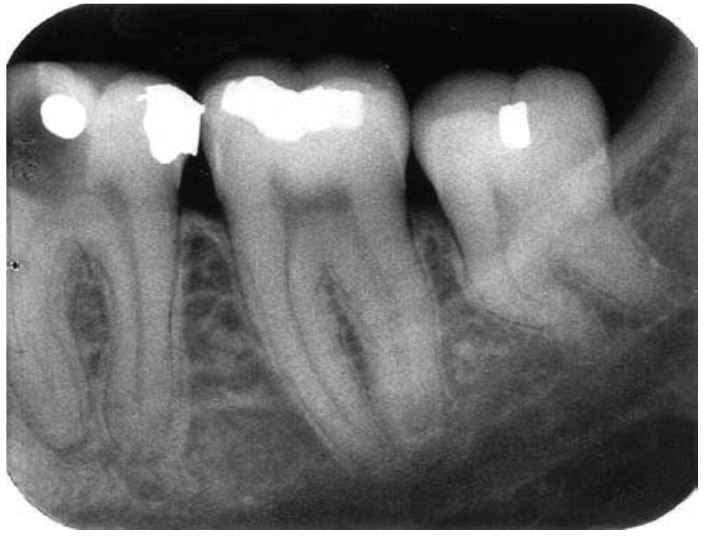

Chân răng dư

Có thể xảy ra trên bất cứ răng nào, nhưng thường gặp nhất là răng khôn, răng nanh dưới và các răng cối nhỏ. Trên phim X quang có thể nghi ngờ chân răng dư khi ống tủy giảm kích thước đột ngột và chia thành 2 ống tủy.

Chân răng dư thường gây ảnh hưởng đến việc điều trị tủy, nhổ răng và chỉnh nha.